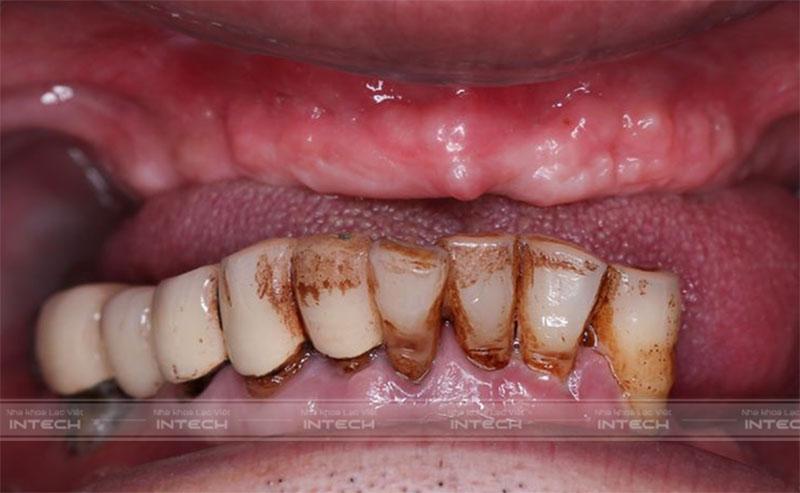

Tình trạng răng trước đây của chú Chu Văn BảyTình trạng răng trước đây của chú Chu Văn Bảy

Khách hàng Chu Văn Bảy (65 tuổi) - Thạch Thất, Hà Nội trước đây bị mất nhiều răng do hút thuốc lá lâu năm cộng với làm cầu răng sứ hỏng. Tình trạng mất răng khiến chú Bảy gặp khó khăn khi ăn nhai, đau đớn và mất tự tin khi giao tiếp.

Hơn chục năm răng lung lay, chú Bảy đã tìm đến phương pháp làm cầu răng sứ với mong muốn cải thiện khả năng ăn nhai. Tuy nhiên, tác động của lực nhai khiến cho cầu răng sứ không thể chịu lực được và gãy dần.

Chú Bảy tâm sự: “Mới đầu răng lung lay và có bị hỏng 1 vài chiếc nên chú đã quyết định đi làm cầu răng sứ tại một cơ sở nha khoa gần nhà. Cứ hỏng 1 cái thì mài 2 cái bên cạnh để làm trụ và lắp cầu răng vào. Thế nhưng sau 7 năm thì nó hỏng nốt cả 2 trụ răng và cuối cùng thì cả 2 hàm của chú gần như không còn khả năng ăn nhai nữa.”

• Mất toàn bộ răng hàm trên và nhiều răng hàm dưới.

• Các răng còn lại ở hàm dưới bị lung lay nặng.

• Đau nhức các răng làm cầu sứ, mất toàn bộ chức năng ăn nhai.